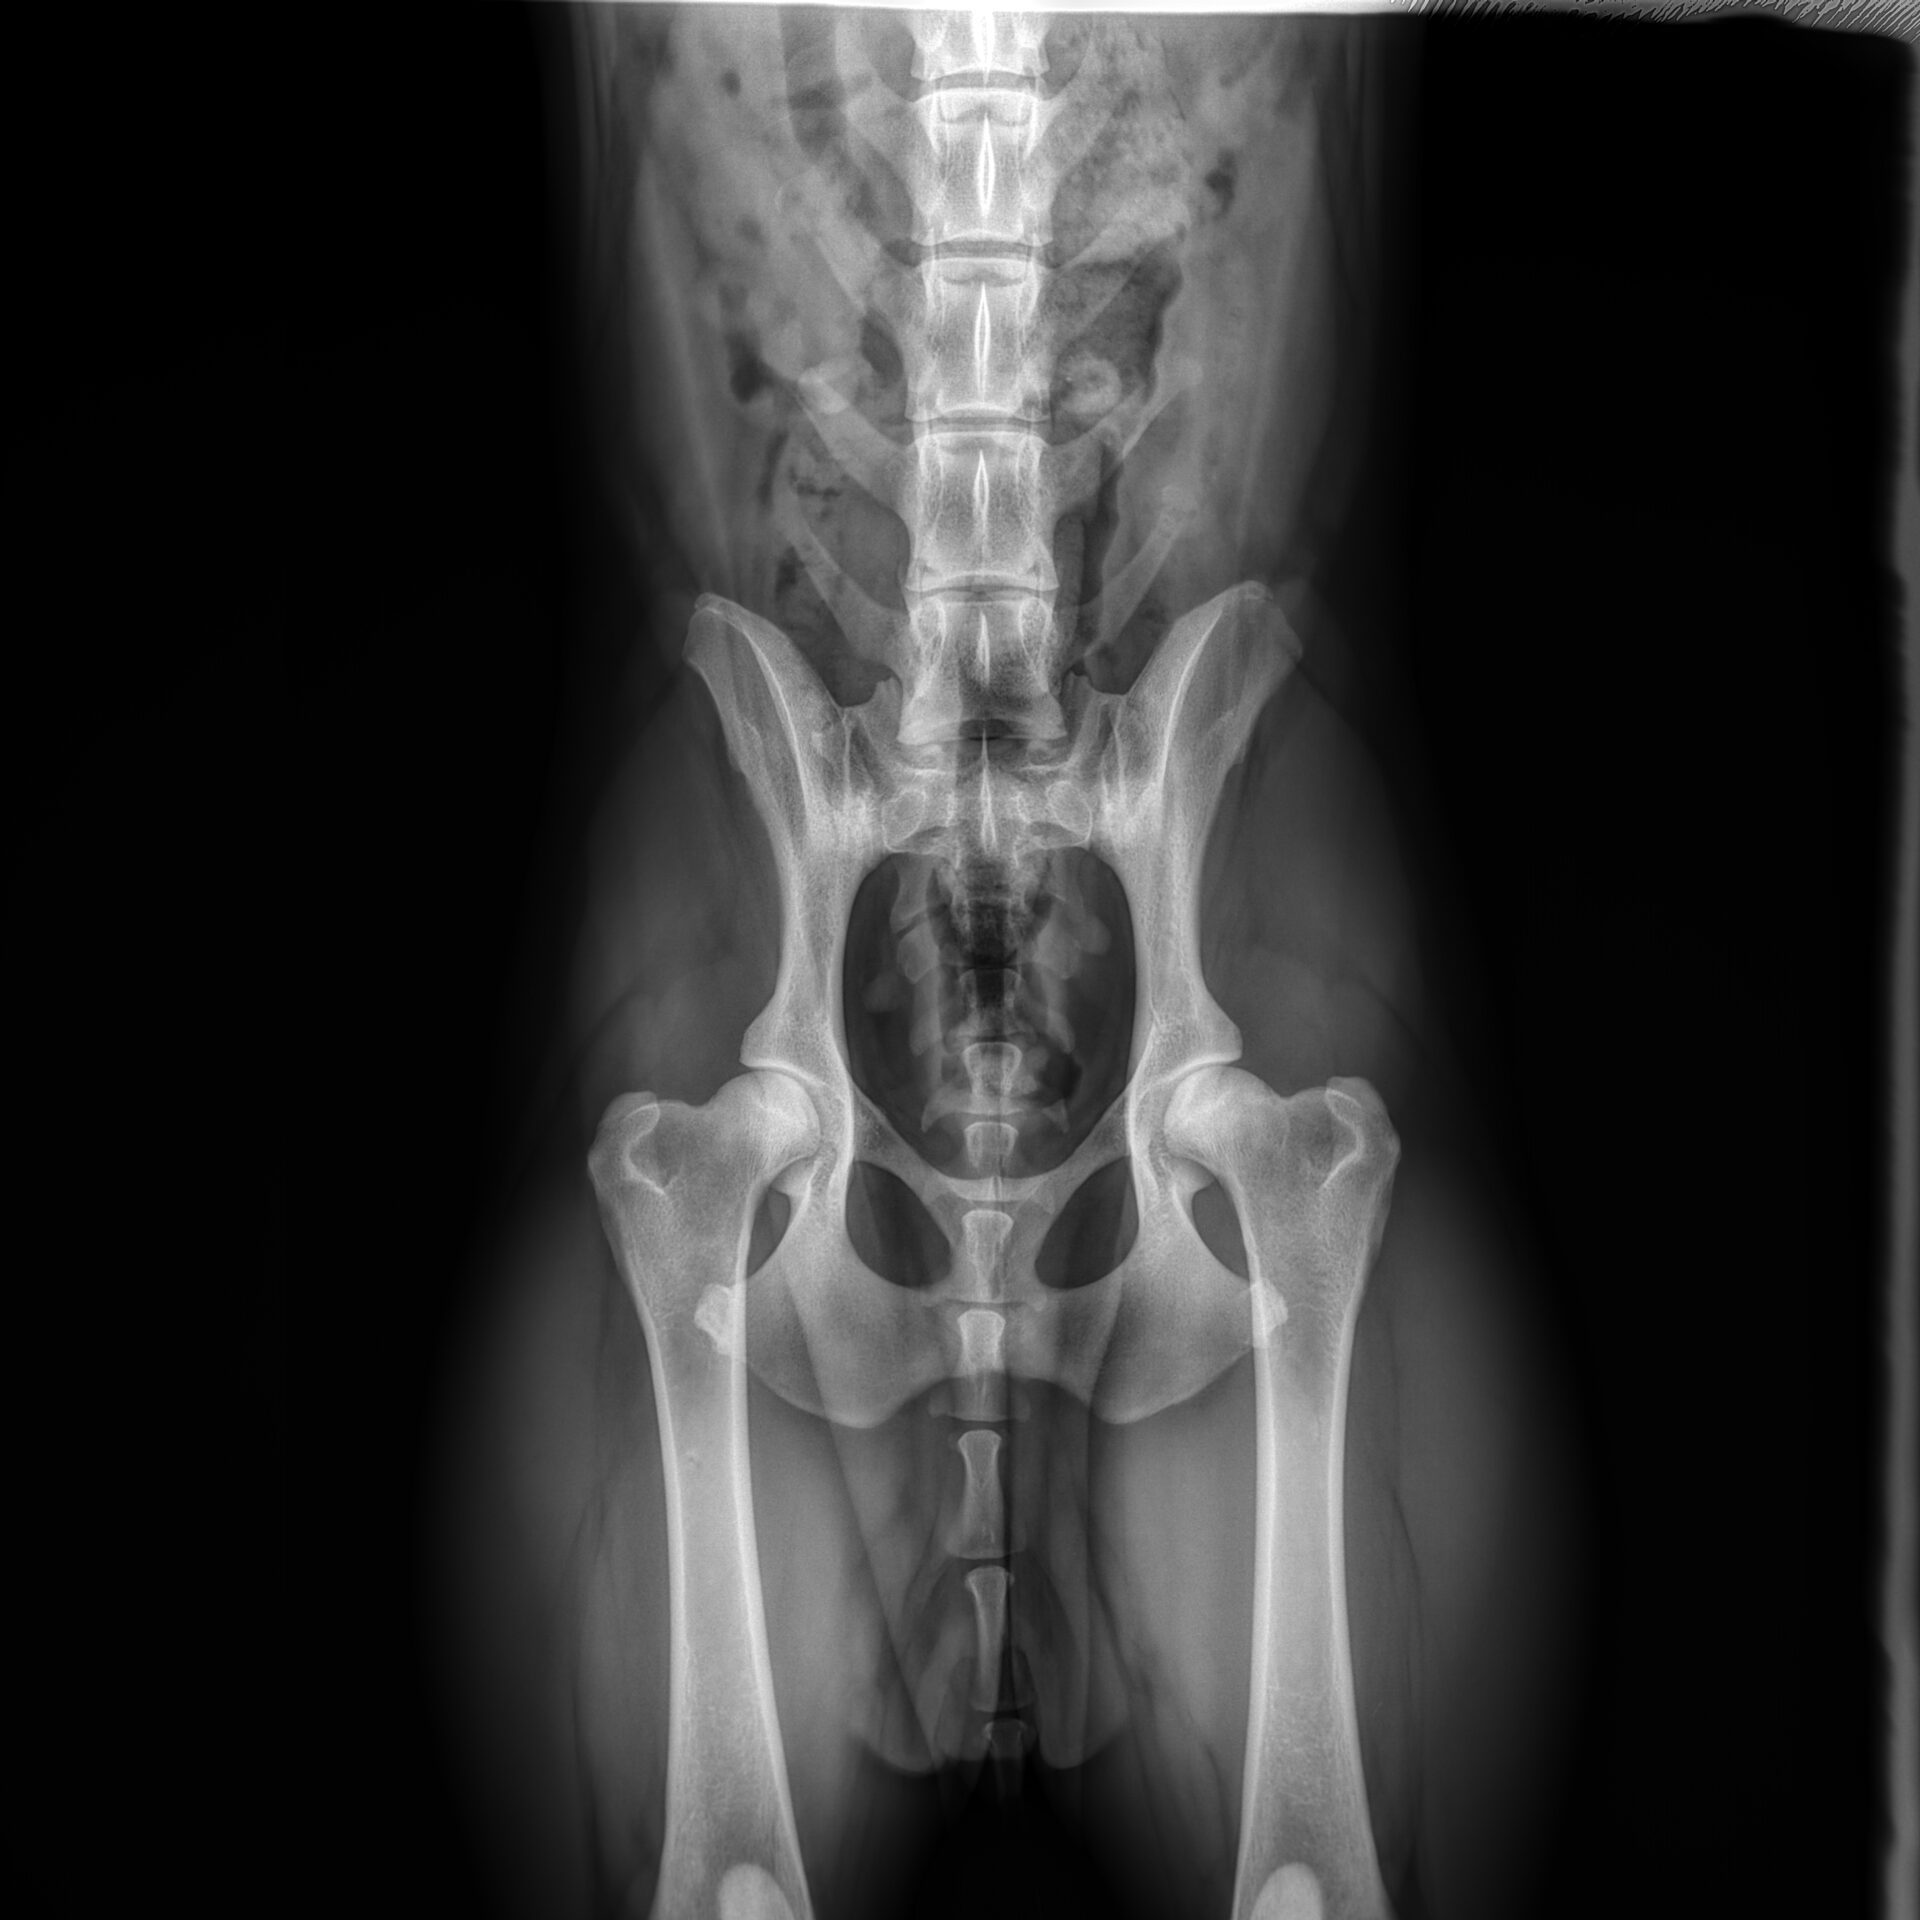

HD: A

rug: 100% (foto’s aanwezig)